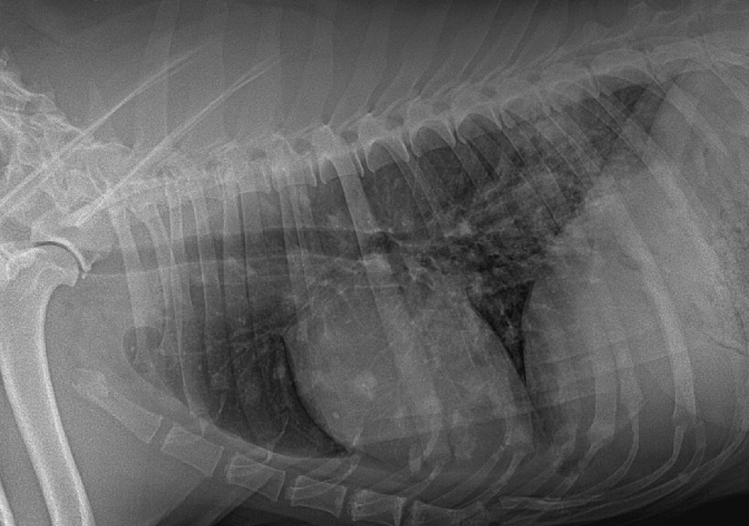

Nodular pattern

multiple rounded opacities

- bronchopneumonia with pre-existing pleural effusion

- the lung has no well-defined margin

With very observable radiopacity nodules

Tuberculosis

Metastases